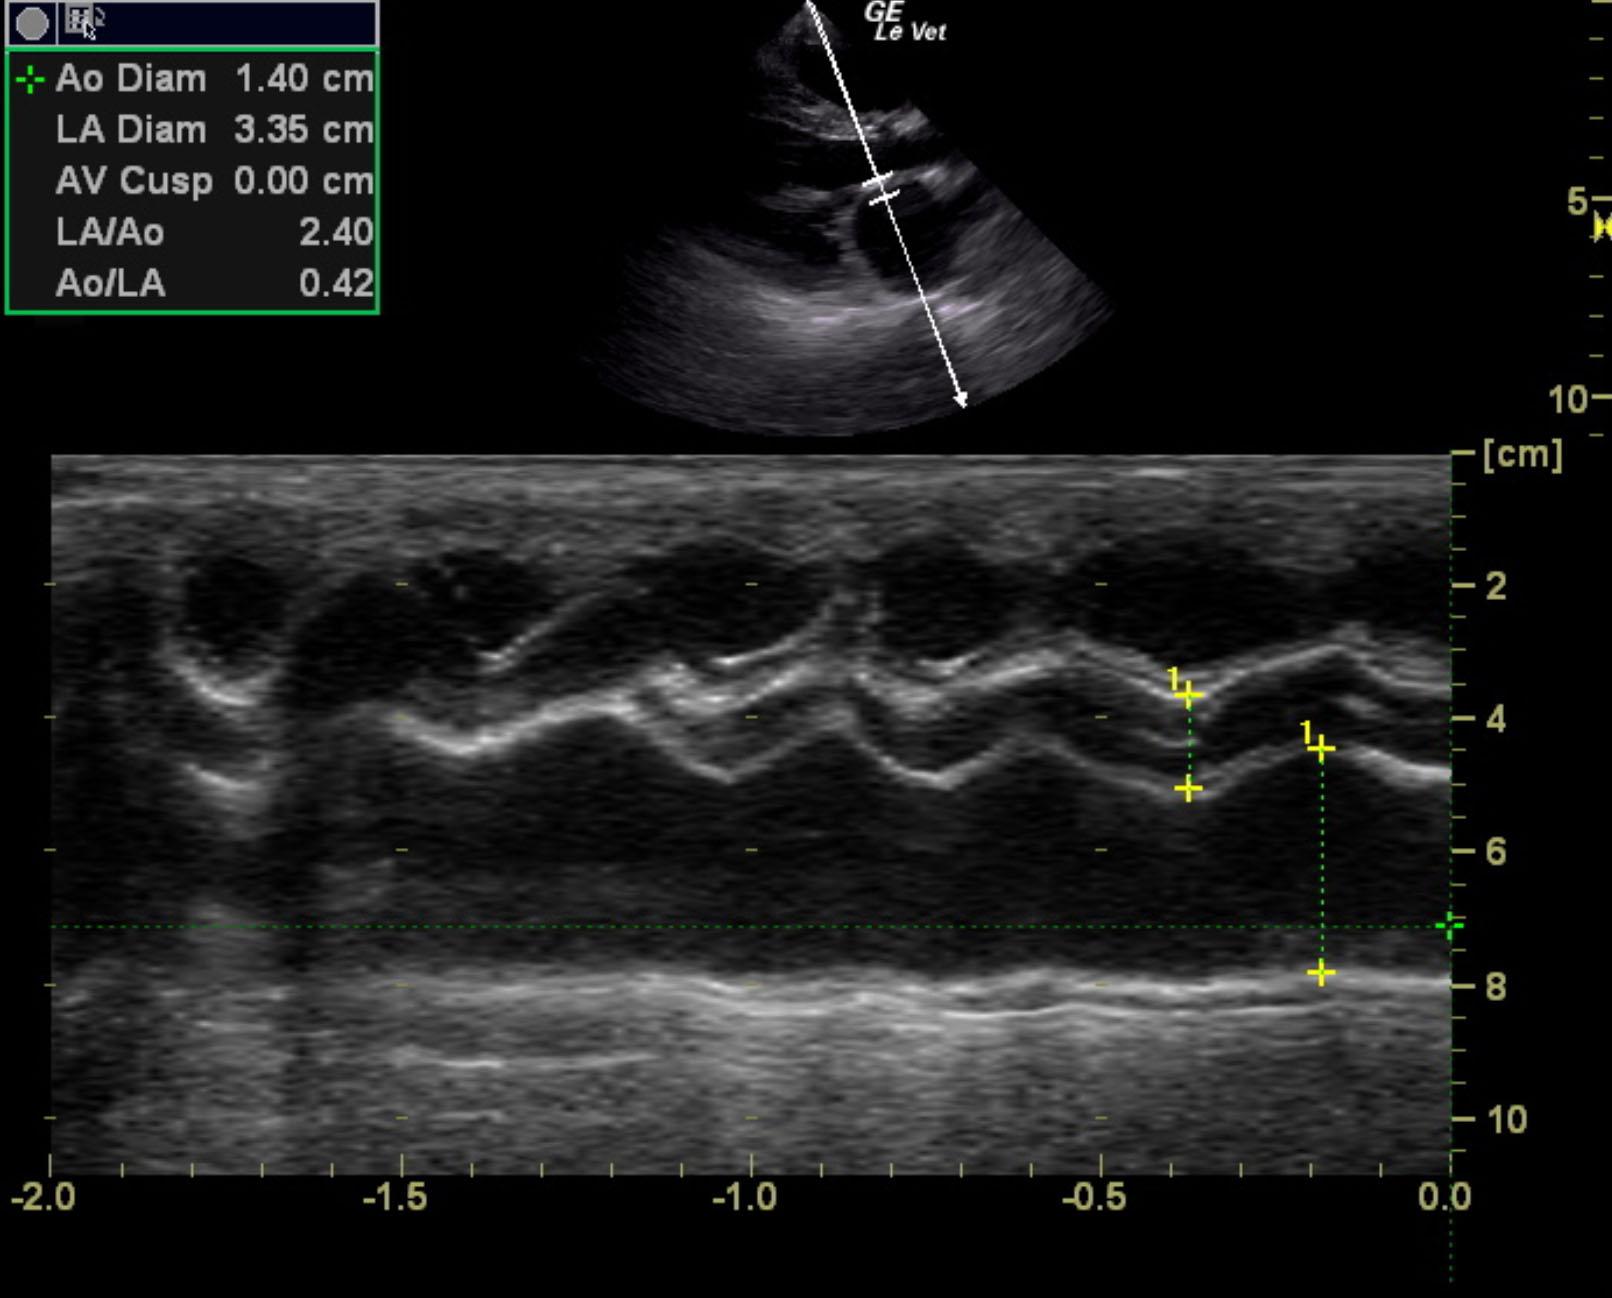

The cardiac presentation revealed moderate left and right sided overload with tricuspid and mitral valve vegetative lesions. Left atrial and right atrial enlargement was noted. Right ventricular overload was noted with flattening of the ventricular septum. Slight prolapse of the anterior mitral valve leaflet was noted. Prolapse of the tricuspid vavle was also noted. Significant pulmonic insufficiency and tricuspid insufficiency was noted. This is consistent with pulmonary hypertension.

Tricuspid insufficiency velocity 3.9 m/sec